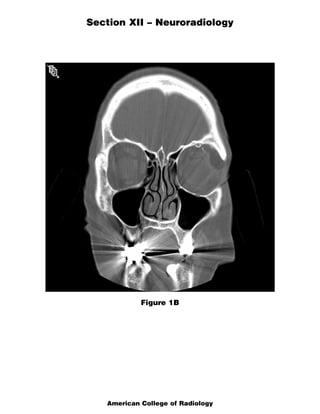

The document discusses several radiology cases involving the brain and spine. Question 291 presents CT scans of a woman with headaches and asks for the most likely diagnosis of a fat-containing extraconal orbital mass. Question 292 shows MR images of a woman with extremity weakness and asks for the most likely diagnosis of multiple brain and spine lesions. Question 293 presents MR images of a man with back pain and asks for the diagnosis of a posterior spinal mass seen on the images.